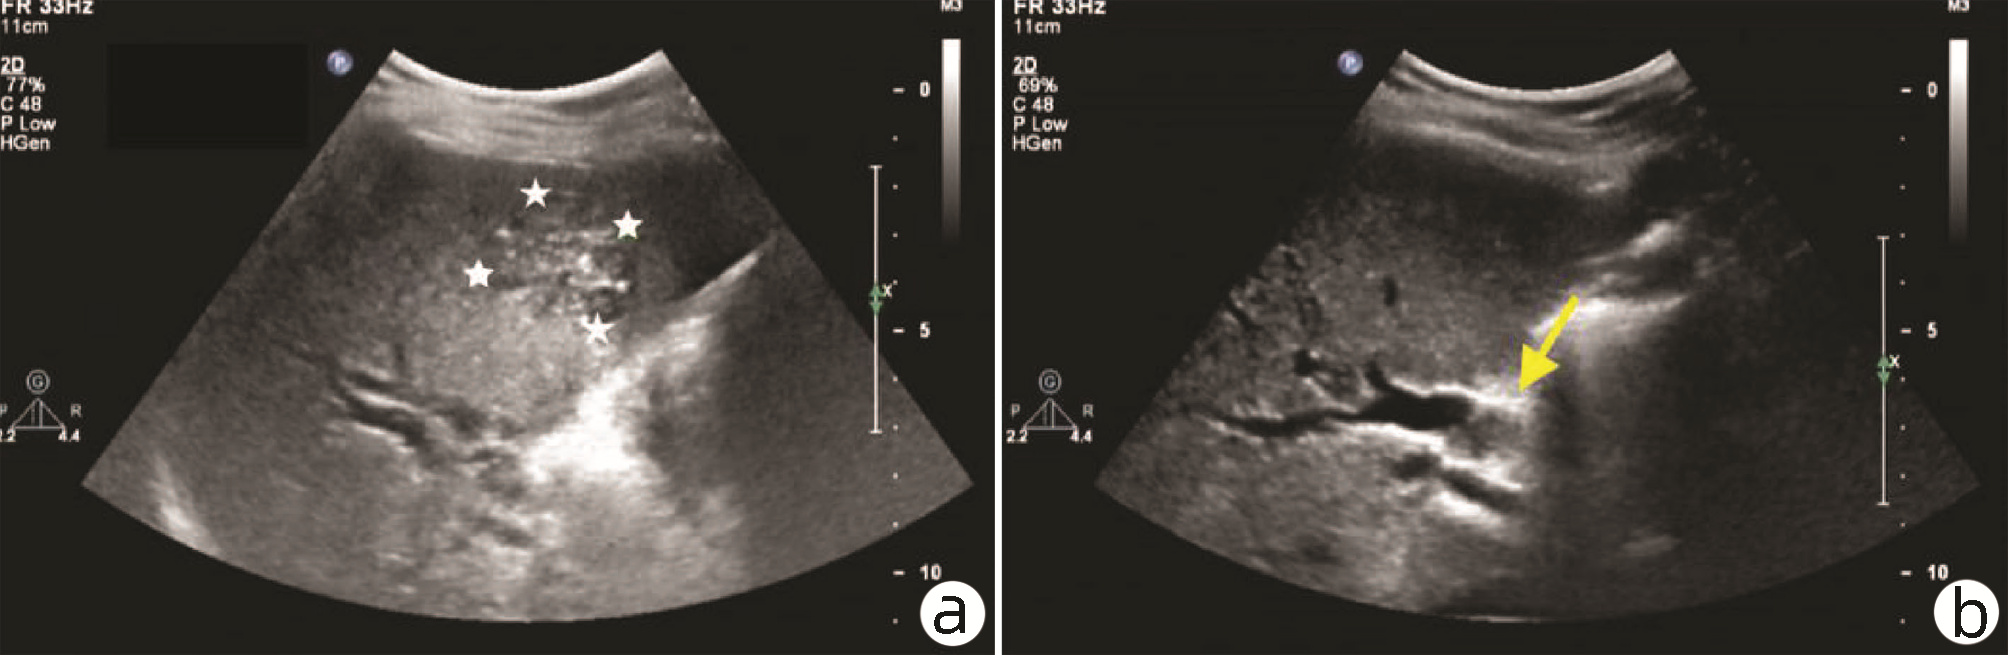

Hepatocellular carcinoma with bile duct tumor thrombus: A case report

Renjie LU, Fangfang SUN, Jie DU, Lirong ZHAO

2022, 38(8): 1872-1874. DOI: 10.3969/j.issn.1001-5256.2022.08.028

Abstract(831) HTML (461) PDF (3665KB)(88)

Abstract: